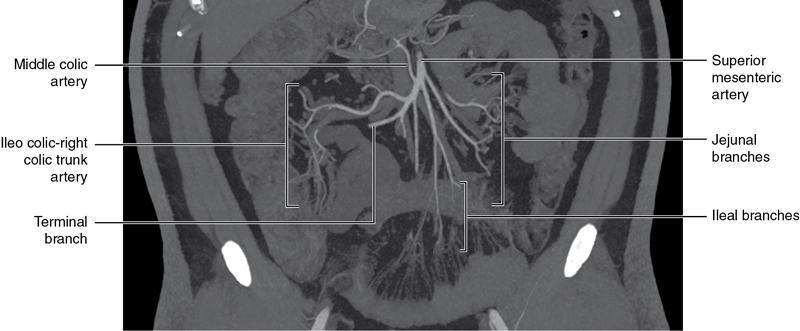

CROSS SECTIONAL ANATOMY OF ABDOMEN Satya Jha NORMAL ANATOMY OF ABDOMEN AND PELVIS Amandeep Singh The two major surfaces: The anterior and posterior layers of the coronary ligament converge on bare area (not covered by peritoneum). Its right and left margins form the right and left triangular ligaments. The right triangular ligament extends toward the diaphragm and separates right subphrenic space from right subhepatic space. The left triangular ligament gives tracts extending to the diaphragm and falciform ligament and does not compartmentalize the left subphrenic space. Ligamentum teres or the obliterated umblical vein is contained in falciform ligament which attaches the liver to anterior abdominal wall. The main portal vein, the proper hepatic artery and the common bile duct are contained within investing peritoneal folds of hepatoduodenal ligament at the porta hepatis (Fig. 7.2.2.1). Liver is divided into eight segments which are functionally independent and have their own vascular supply and biliary drainage. Arterial circulation: The branches of the hepatic artery accompanying the portal veins. Hepatic venous system: The right, middle, and left hepatic veins draining into IVC (Figs. 7.2.2.2 and 7.2.2.3). The gallbladder is a blind pear-shaped muscular membranous sac which is an embryologic derivative of the foregut, is a pouch lying along the undersurface of the liver. The gallbladder fossa is located in the plane of the interlobar fissure, which lies between the right and left hepatic lobes. Its major function is to store and concentrate bile which is produced by the liver. It measures approximately 4 cm in diameter when it is normally distended. Gallbladder is a smaller tubular structure in contracted state. The normal gallbladder wall thickness ranges from 1 to 3 mm. The gallbladder is divided into the fundus, body and neck. Infundibulum is present in the region of neck of the gallbladder, which is called the Hartmann pouch, where gallstones are usually impacted. Intrahepatic biliary radicles (IHBRs) scattered throughout the liver get confluent towards the hilum. They unite to form the right and left main hepatic ducts which further unite to form common hepatic duct (CHD) at the hilum. Common bile duct is formed by the union of cystic duct with common hepatic duct. The main pancreatic duct is joined with the common bile duct to form the ampulla of Vater at the major duodenal papilla (Figs. 7.2.2.4 and 7.2.2.5). Pancreas is located in anterior pararenal space of retroperitoneum anterior to perirenal (Gerota’s) fascia and posterior to parietal peritoneum. It is divided into head, uncinate process, neck, body and tail from right to left. Pancreas lies anterior to portal vein, which marks the point of transition between the body and neck. The region between head of pancreas and second and third parts of duodenum is known as the pancreatic groove. In postnephrectomy cases or with agenesis of kidney or ectopic kidney, pancreas moves posteriorly to partially fill in the empty renal fossa; its soft tissue density should not be mistaken for recurrent tumour. It is located in the pancreatic groove and is bounded superiorly by the duodenal bulb, laterally by second portion of duodenum, inferiorly by third portion of duodenum, medially by superior mesenteric vein and anterior to inferior vena cava. It is a wedge or wedge shaped lying posterior to superior mesenteric artery and vein. It is an imaginary junction between the head and body and lies directly over the junction of the splenic vein and superior mesenteric vein. It is located posterior to the lesser sac and anterior to the aorta, left adrenal gland, left kidney, and renal vessels and runs obliquely upward to the left of the superior mesenteric vessels. It is situated median to the colonic flexure and anterior to the left kidney. It is located in close proximity to the splenic hilum without a notable relation with the body of pancreas. It is seen anterior to the left kidney and median to the colonic flexure. The distal part of the tail passes between the peritoneal layers of the splenorenal ligament (Fig. 7.2.2.6 and 7.2.2.7).